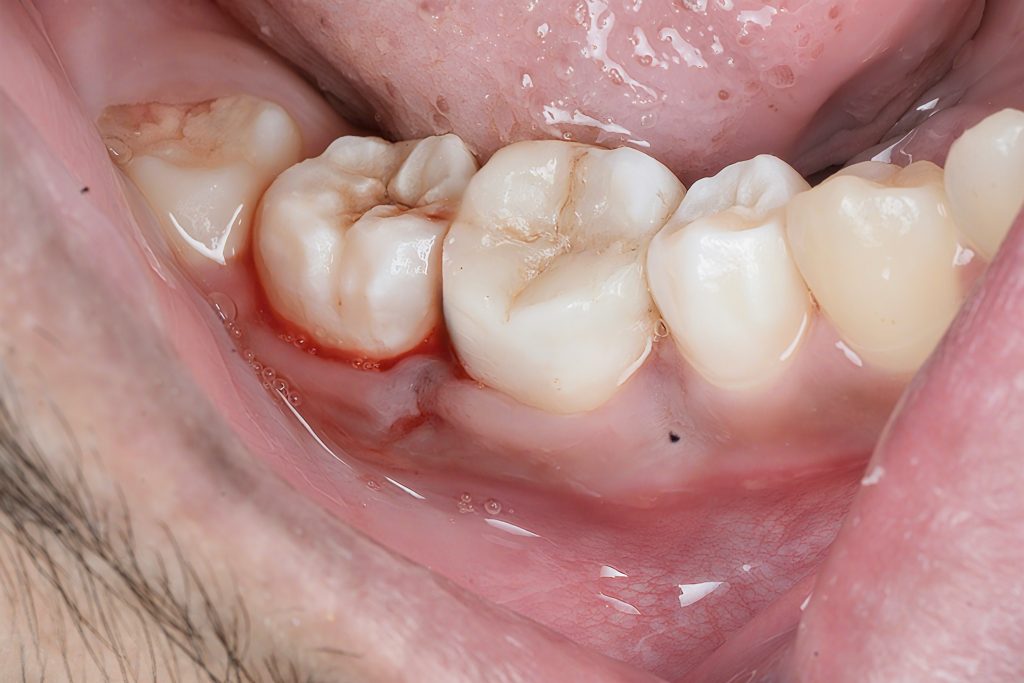

Clinical

- Localized swelling and mild gingival inflammation around the affected tooth.

- Deep carious breakdown extending into the dentin.

- Cracked undermined marginal ridges.

- Heavy occlusal staining with food stagnation.

Decay mapping under magnification revealed extensive undermining of the pulpal floor and mesiobuccal wall.

High-definition images documented caries severity for the patient and the record (Kudom verified).